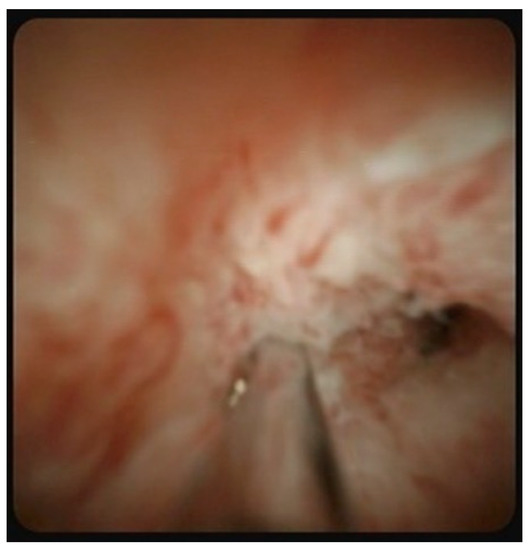

2.4. Endoscopic Procedures